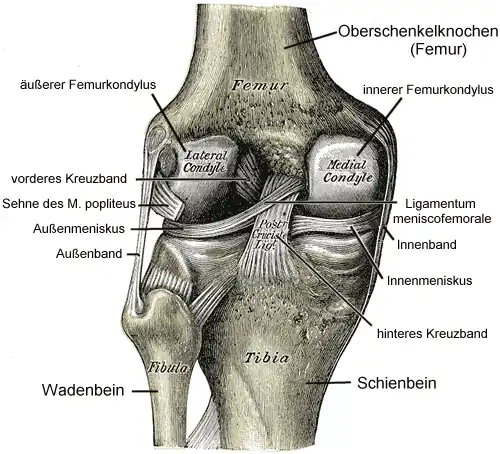

Das Kniegelenk (lateinisch Articulatio genus) ist das im Knie (lateinisch Genu, altgriechisch γόνυ gony) befindliche größte Gelenk der Säugetiere. Der Oberschenkelknochen (Femur), das Schienbein (Tibia) und die Kniescheibe (Patella) bilden dabei die knöchernen Gelenkkörper.

Das Kniegelenk ist ein zusammengesetztes Gelenk. Es besteht aus zwei Einzelgelenken, dem Kniescheibengelenk (Articulatio femoropatellaris), welches sich zwischen Oberschenkelknochen und Kniescheibe befindet, und dem Kniekehlgelenk (Articulatio femorotibialis), das zwischen Oberschenkelknochen und Schienbeinkopf (Caput tibiae) liegt. Anatomisch gesehen handelt es sich bei dem proximalen Gelenk zwischen Schienbein (Tibia) und Wadenbein (Fibula) (Articulatio tibiofibularis) zwar um ein eigenständiges Gelenk, das aber in der Regel über eine Ausbuchtung der Kniegelenkkapsel (Recessus subpopliteus) mit dem Kniegelenk verbunden ist.

Bänder

Da das Knie durch seine knöcherne Konstruktion sehr instabil ist, wird es durch zahlreiche Bänder gesichert. Sie verstärken damit die Gelenkkapsel, in deren äußere Schicht sie in der Regel eingebaut sind. Die Bänder des Knies werden nach ihrer Lage in vordere (ventrale), seitliche (kollaterale), hintere (dorsale) und zentrale Bänder eingeteilt.

Zentrale Bandsicherung

Die Kreuzbänder (Ligamenta cruciata) ziehen von der Grube zwischen den Oberschenkelknorren zum Schienbein. Von der Seite und von vorn betrachtet überkreuzen sie sich dabei in ihrem Verlauf.

Menisken

Da die miteinander in Verbindung stehenden (artikulierenden) Gelenkflächen nicht genau aufeinander passen, wird diese „Ungleichheit“ (Inkongruenz) durch halbmondförmige Faserknorpelscheiben, die Menisken ausgeglichen, die den Drehbewegungen folgen können. Eine weitere Aufgabe der Menisken besteht in der Vergrößerung der Kontaktfläche zwischen Schienbein und Oberschenkelknochen.

Man unterscheidet einen Innenmeniskus (Meniscus medialis), der C-förmig, größer und etwas unbeweglicher (da mit dem Innenband verwachsen) ist, und einen Außenmeniskus (Meniscus lateralis), der kreisförmig, kleiner und beweglicher ist (da er mit keinem Seitenband verwachsen ist). Die Menisken sind im Querschnitt keilförmig. Die hohe Kante liegt außen, die niedrige innen. Da die Oberschenkelknochen genau in der Mitte direkt auf dem Schienbeinplateau und peripher auf den Menisken aufliegen, tragen diese einen wesentlichen Teil der Last.